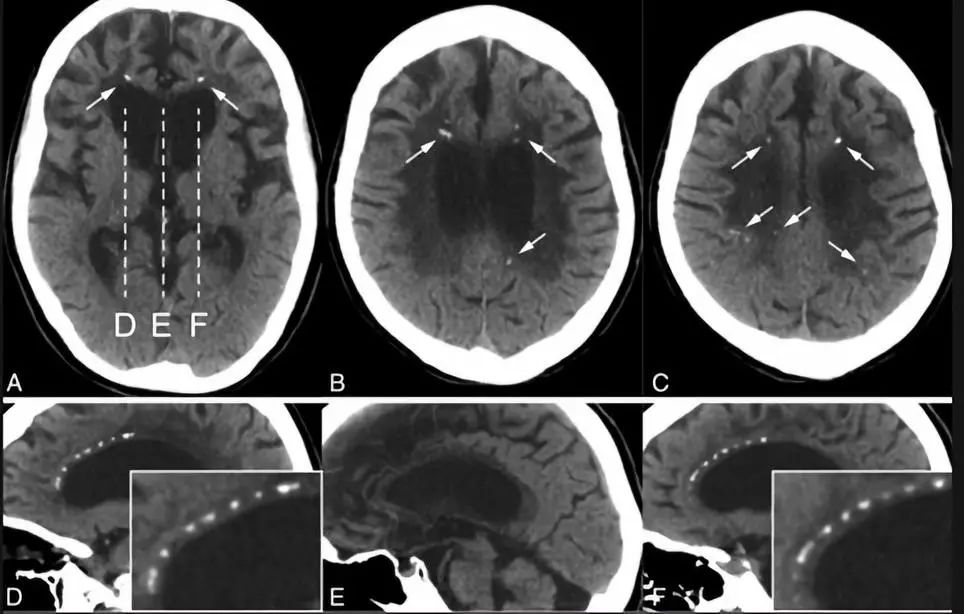

囊虫的钙化形态各异,取决于脑囊虫四个主要阶段(也称为Escobar的病理阶段):a囊泡期:活的寄生虫有完整的包囊膜,囊壁光滑,内可见头节,无强化。因此没有宿主反应。b胶状囊泡期:包囊破溃,包囊的液体渗入组织,周围有水肿。此期引发强烈的免疫反应,所以此期的临床反应最重。见下图。

c颗粒结节期:随着囊肿进一步变性缩小,水肿减轻;增强仍存在。d结节钙化期:终末期,静止的钙化囊残余;没有水肿。

脑囊虫可以累及CNS系统各个部位: